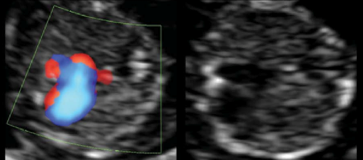

Ειδικά για την καρδιά, η συγκέντρωση αυτών των πρόδρομων κυττάρων δίνει γέννηση στον πρόδρομο καρδιακό σωλήνα (εικ.1) ήδη από την 21η ημέρα μετά τη σύλληψη. Ο καρδιακός αυτός σωλήνας διαθέτει ήδη φλεβικό και αρτηριακό πόλο1. Τις αμέσως επόμενες ημέρες, ο καρδιακός αυτός σωλήνας υφίσταται δύο κάμψεις-αναδιπλώσεις, όπως φαίνεται σχηματικά στην εικ. 1, στο τέλος των οποίων αποκτά ένα σχήμα στο οποίο κανείς μπορεί να διακρίνει τις βασικές κοιλότητες που συγκροτούν την καρδιά. Η διαδικασία αυτή ολοκληρώνεται την 24η-25η ημέρα, μετά τη σύλληψη. Ο σχηματισμός της καρδιάς συνεχίζεται τις επόμενες εβδομάδες (εικ. 2), με ολοκλήρωση του μεσοκολπικού και μεσοκοιλιακού διαφράγματος καθώς και με την διαίρεση του μονήρους αρτηριακού μίσχου σε δύο μεγάλα αγγεία. Με την βοήθεια των υπερήχων, μπορούμε ήδη από την 15η εβδομάδα κύησης να αναγνωρίσουμε τις βασικές δομές που συγκροτούν την καρδιά (εικ. 3)και να διαγνώσουμε μεγάλο ποσοστό από ανωμαλίες, που ενδέχεται – ευτυχώς σπάνια – να επηρεάσουν αυτή τη διαδικασία διαμόρφωσης του οργάνου. Παράλληλα με την διαδικασία δομικής διαμόρφωσης της καρδιάς, ήδη από την 3η εβδομάδα σχηματισμού, ο καρδιακός σωλήνας παρουσιάζει περισταλτικού τύπου συσπάσεις 2, ενώ όπως αποτελεί πρακτική σε κάθε μαιευτικό ιατρείο, από την 8η-9η εβδομάδα κύησης, μπορούμε με την βοήθεια των υπερήχων να ανιχνεύσουμε τον περισταλτισμό της καρδιάς, επιβεβαιώνοντας έτσι μία φυσιολογικά εξελισσόμενη ενδομήτρια κύηση.

Εικ.3. Ηχοκαρδιογράφημα καρδιάς εμβρύου σε ηλικία 15 εβδομάδων